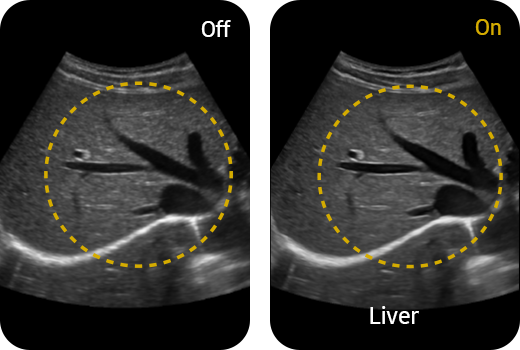

HQ-Vision™ ¹ provides clearer images by mitigating the characteristics of ultrasound images that are slightly blurred than the actual vision.

Reduce noise to improve